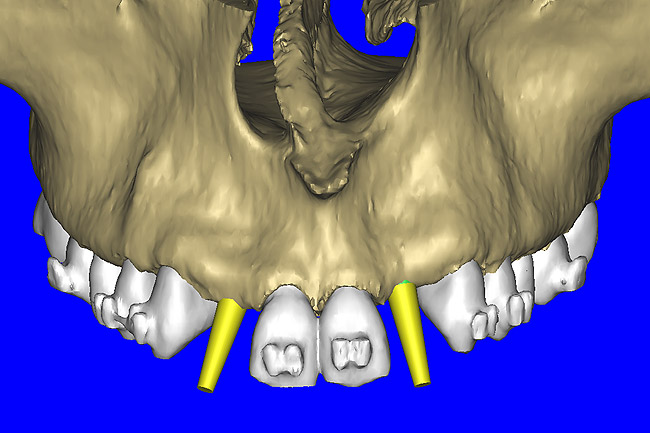

After the basic plan had been established, it was re-evaluated using interactive 3D images. The reconstructed 3D view of the maxilla clearly illustrated the extent of the bilateral facial concavities, and the root eminences of the adjacent and posterior teeth (Figure 7A). The placement of the virtual implants then was evaluated to ensure that the facial cortical plate was not perforated (Figure 7B). The implants were labeled individually as “7” and “10,” with the simulated yellow abutment projection indicating the facial-lingual inclination through the bone to the level above the incisal edge of adjacent teeth. The ability to gain a better understanding of these individual root forms can not be underestimated. The dental literature has suggested certain parameters for placing implants near teeth and implants next to other implants. However, there is little scientific 3D documentation to support these suggested rules.5-10 The use of an interactive treatment-planning software application permits closer scrutiny of previously difficult-to-visualize areas, and can now be used to redefine perceptions of spatial positioning of implants, especially when in close proximity to natural tooth roots, vital anatomy, and adjacent implants.27-29

Figure 7b  The 3D reconstruction showed (A) the facial concavities and root eminences, and allowed (B) for evaluation of virtual implant placement to ensure the facial cortical plate was not perforated.

Figure 7b